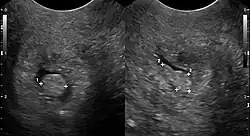

Gallenblase

Beschrieben werden Cholesterolpolypen in der Gallenblase.